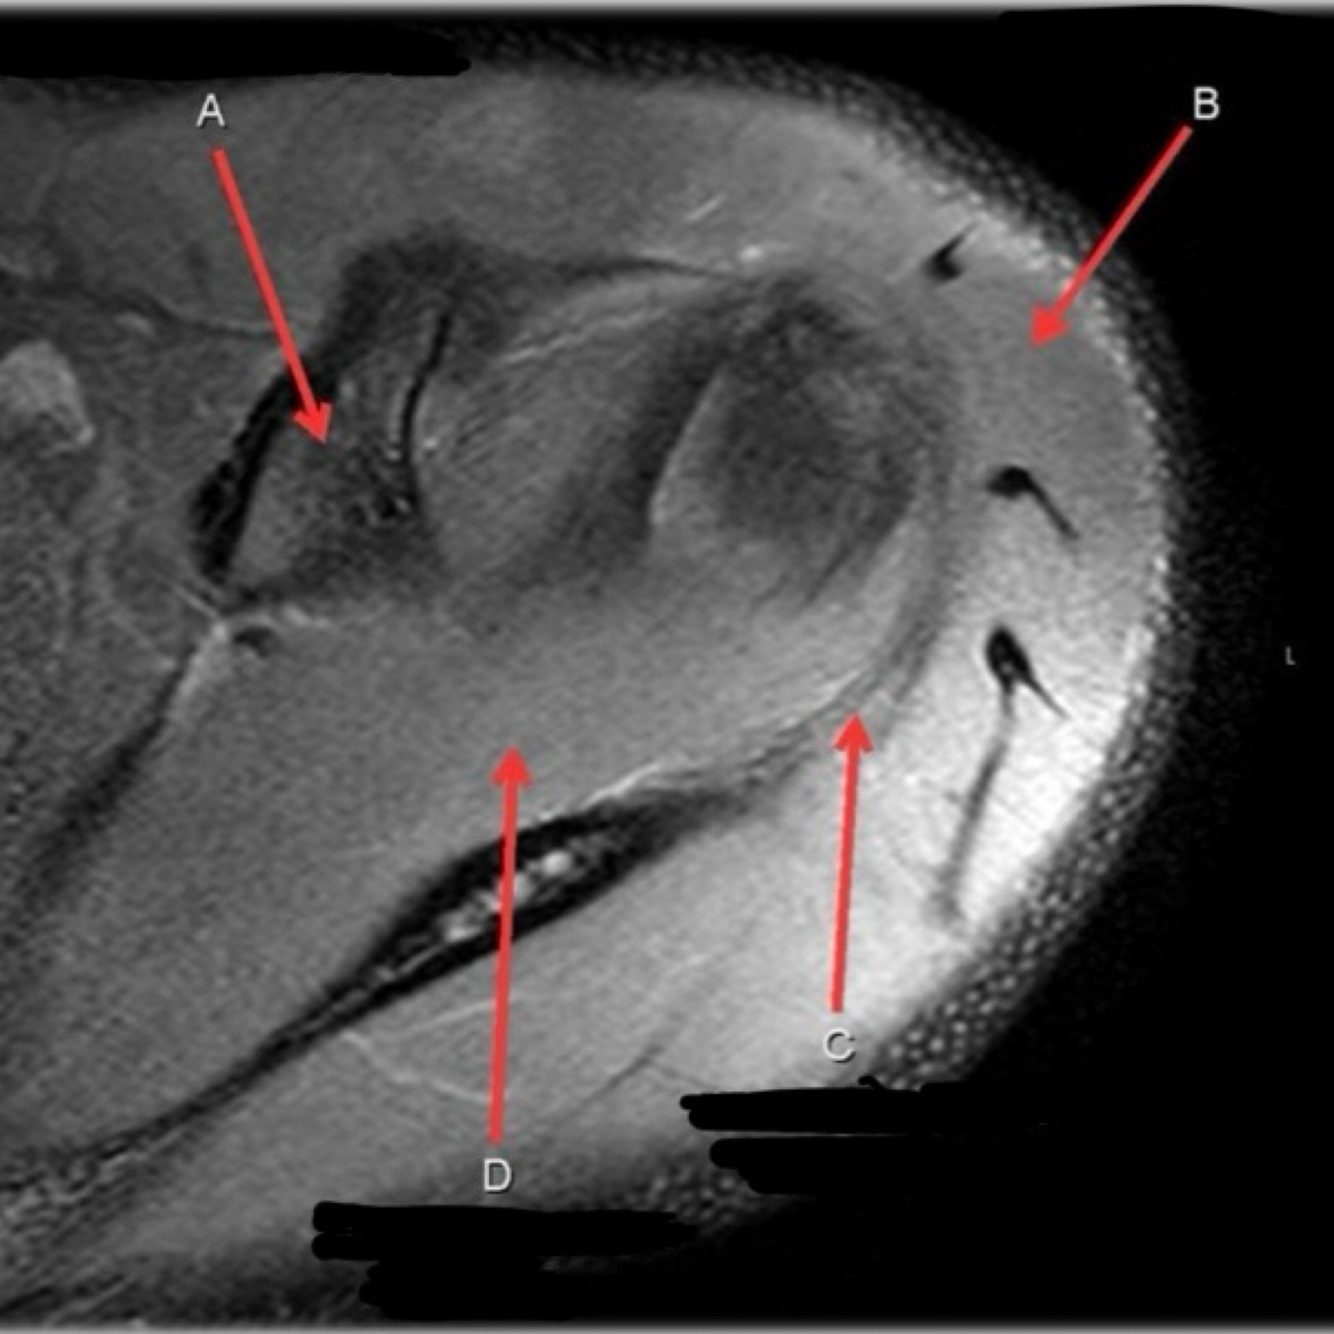

1

Not at all

2

3

4

5

Perfectly

11

Q

What is letter A?

A

ANTERIOR LABRUM